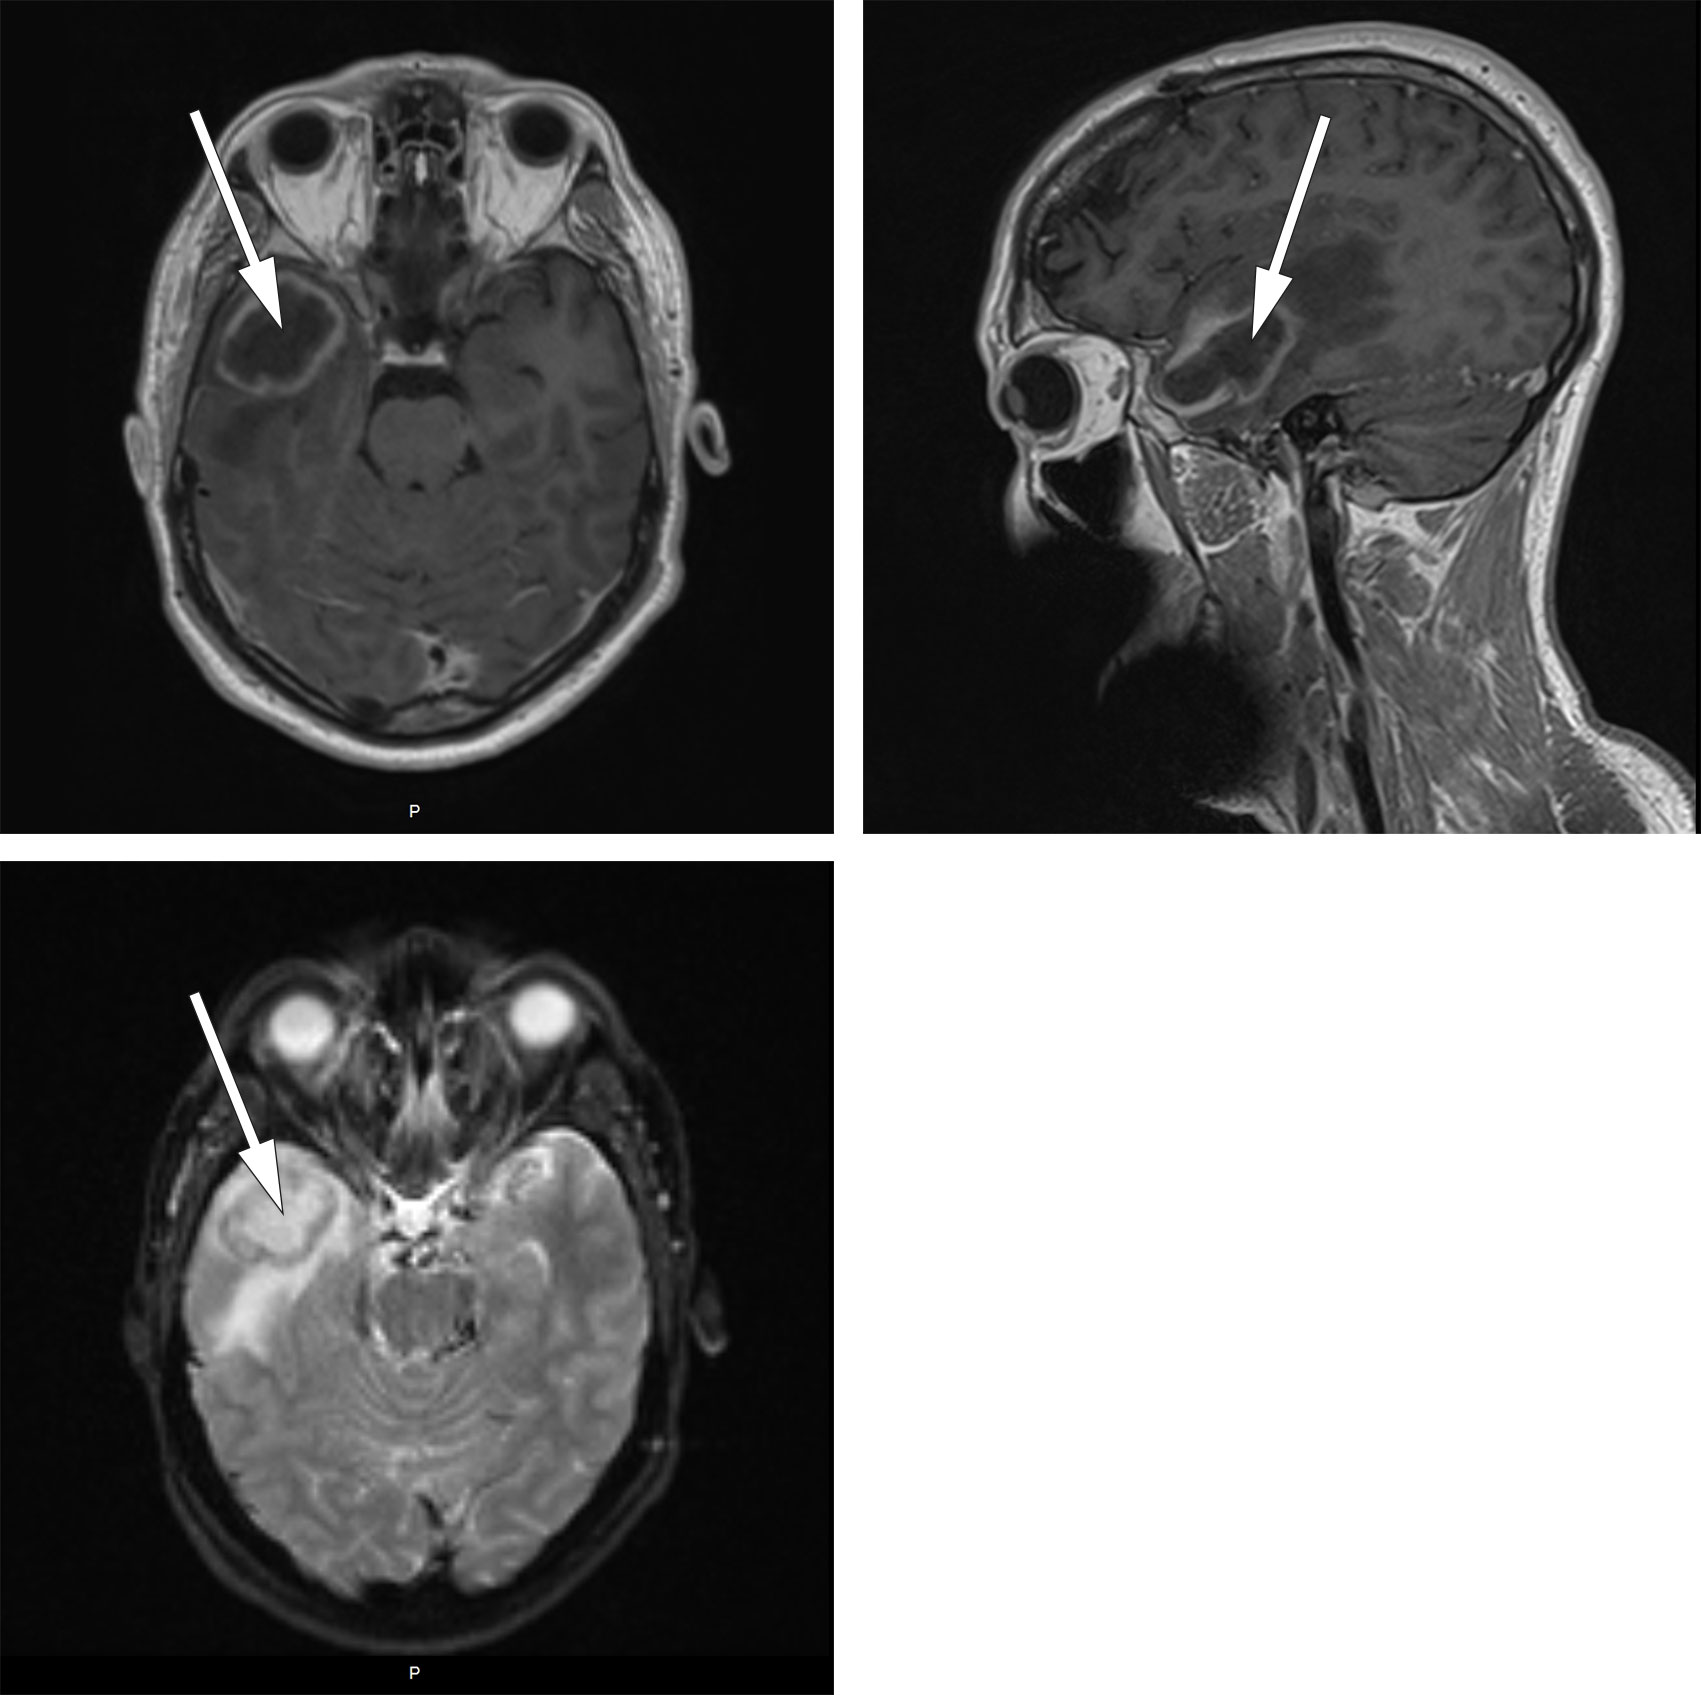

Ved lokalsykehuset var respirasjonen ubesværet, blodtrykket 130/75 mmHg, pulsen 95 slag/min og temperaturen på 39,3 °C. Han var lyssky og nakkestiv. Glasgow Coma Scale (GCS)-skår var 14 med lukkede øyne på grunn av lysskyhet. Blodprøvene viste leukocytter 11,9 × 109/L (referanseområde 3,5–10,0 × 109/L), nøytrofile granulocytter 9,6 × 109/L (1,5–7,3 × 109/L) og CRP 24 mg/L (< 4). Arteriell blodgass uten oksygentilskudd viste hypoksemi med pO2 8,1 kPa (11,0–14,0), men det ble ikke utredet videre pga. hastesituasjon. Blodkulturer og nasofarynksbakteriologi var begge uten senere oppvekst, og han var negativ for pneumokokkantigen i urin. Det ble ikke tatt røntgen toraks. På bakgrunn av sykehistorie med tidligere hjerneabscess ble det gjort CT caput før planlagt spinalpunksjon. CT-undersøkelsen viste en kontrastladende lesjon i høyre temporallapp og tegn på ødem og økt intrakranialt trykk. Intravenøs cefotaksim 3 g × 4 og intravenøs metronidazol 1,5 g × 1 ble igangsatt på mistanke om hjerneabscess, og han ble ikke spinalpunktert. Han ble raskt overflyttet til nevrokirurgisk avdeling ved et universitetssykehus. MR caput samme kveld viste en kontrastladende lesjon med perifokalt ødem i høyre temporallapp (figur 1).

MR caput med kontrast er nødvendig for å stille diagnosen, da det skiller abscess fra andre tilstander som malign tumor, men i praksis vil CT caput ofte tas først (4). Lesjonen framstår på CT som ringformet med kontrastopptak rundt (5). På MR caput med kontrast finner man diffusjonsrestriksjon på diffusjonsvektede sekvenser (diffusion weighted imaging, DWI) og en indre hyperintens og ytre hypointens kant på susceptibilitetsvektede MR-bilder (SWI-magnitude) (6).

MR caput med intravenøs kontrast bekreftet funnet (figur 6). Han ble reoperert dagen etter i narkose med rekraniotomi og fjerning av abscess med kapsel. Pasienten kom seg raskt etter operasjonen uten nevrologiske utfall.